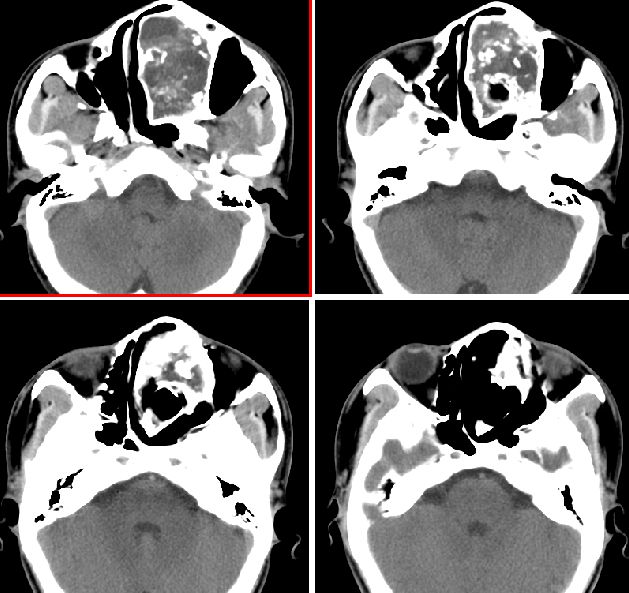

男性,20岁,面部包块8年余,进行性增大

我们考虑来源于上颌骨的骨化性纤维瘤,请大家指教

左侧鼻腔内囊性膨胀性骨质破坏,内示多发点环状钙化,周边骨质硬化.局部与上颌相连部骨质呈毛玻璃样改变.

考虑良性病变;1,上颌骨来源向鼻腔生长,软骨类肿瘤.2,骨化性纤维瘤.3,鼻腔霉菌感染.

左侧鼻腔内囊性膨胀性骨质破坏,内示多发点环状钙化,周边骨质硬化.

良性病变。骨化性纤维瘤首先考虑。